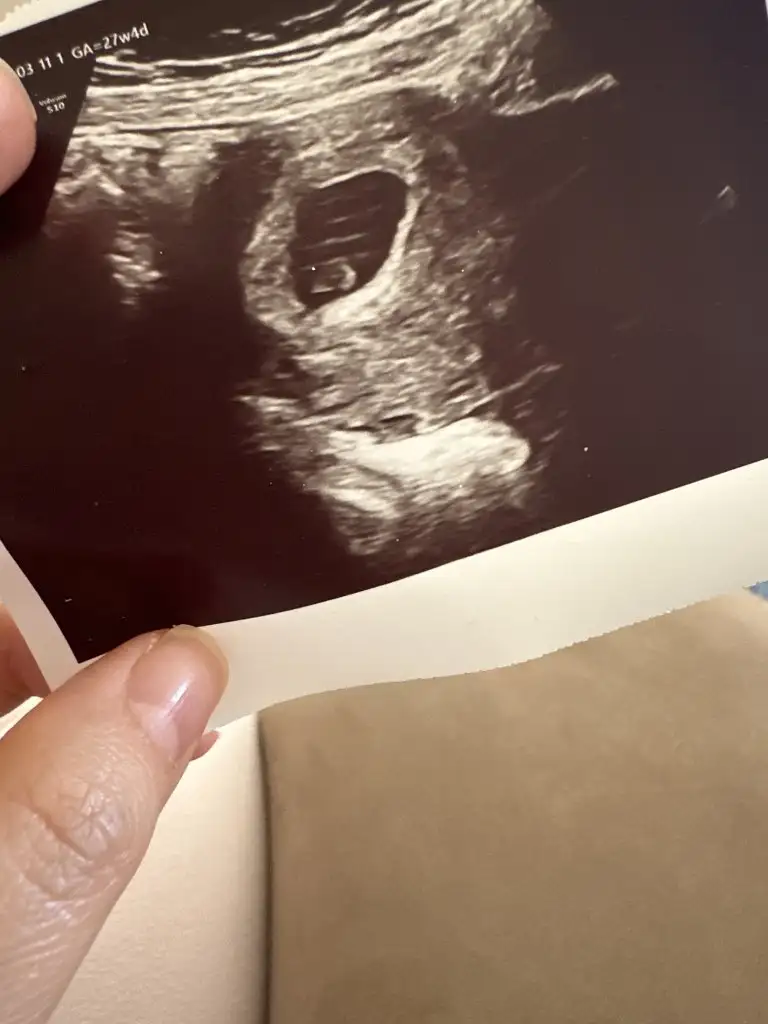

Merhaba kızlar, bende bugün muayeneye gttim devlette, yarın özel hastanede doğumu planlamayı düşündüğüm doktor ile ilk randevumuz olacak. Herşey yolunda dedi. Kan ve idrar testi sonuçların güzel dedi. Kalp atışlarını yine gösterdi, dinletmedi. 12. Haftaya kadar gelmene gerek yok dedi. Başta kanama alanların vardı, geçmiş.. hepinizin de güzel haberler aldığınız bir gün/hafta olsun inşallah🥰 Allah kimsenin emeğini boşa çıkarmasın🙏🏻 bugün fotoğrafta çektirdik☺️ ekliyorum teyzeleri.. sata göre 6+4, ultrasona göre 6+2 imiş.